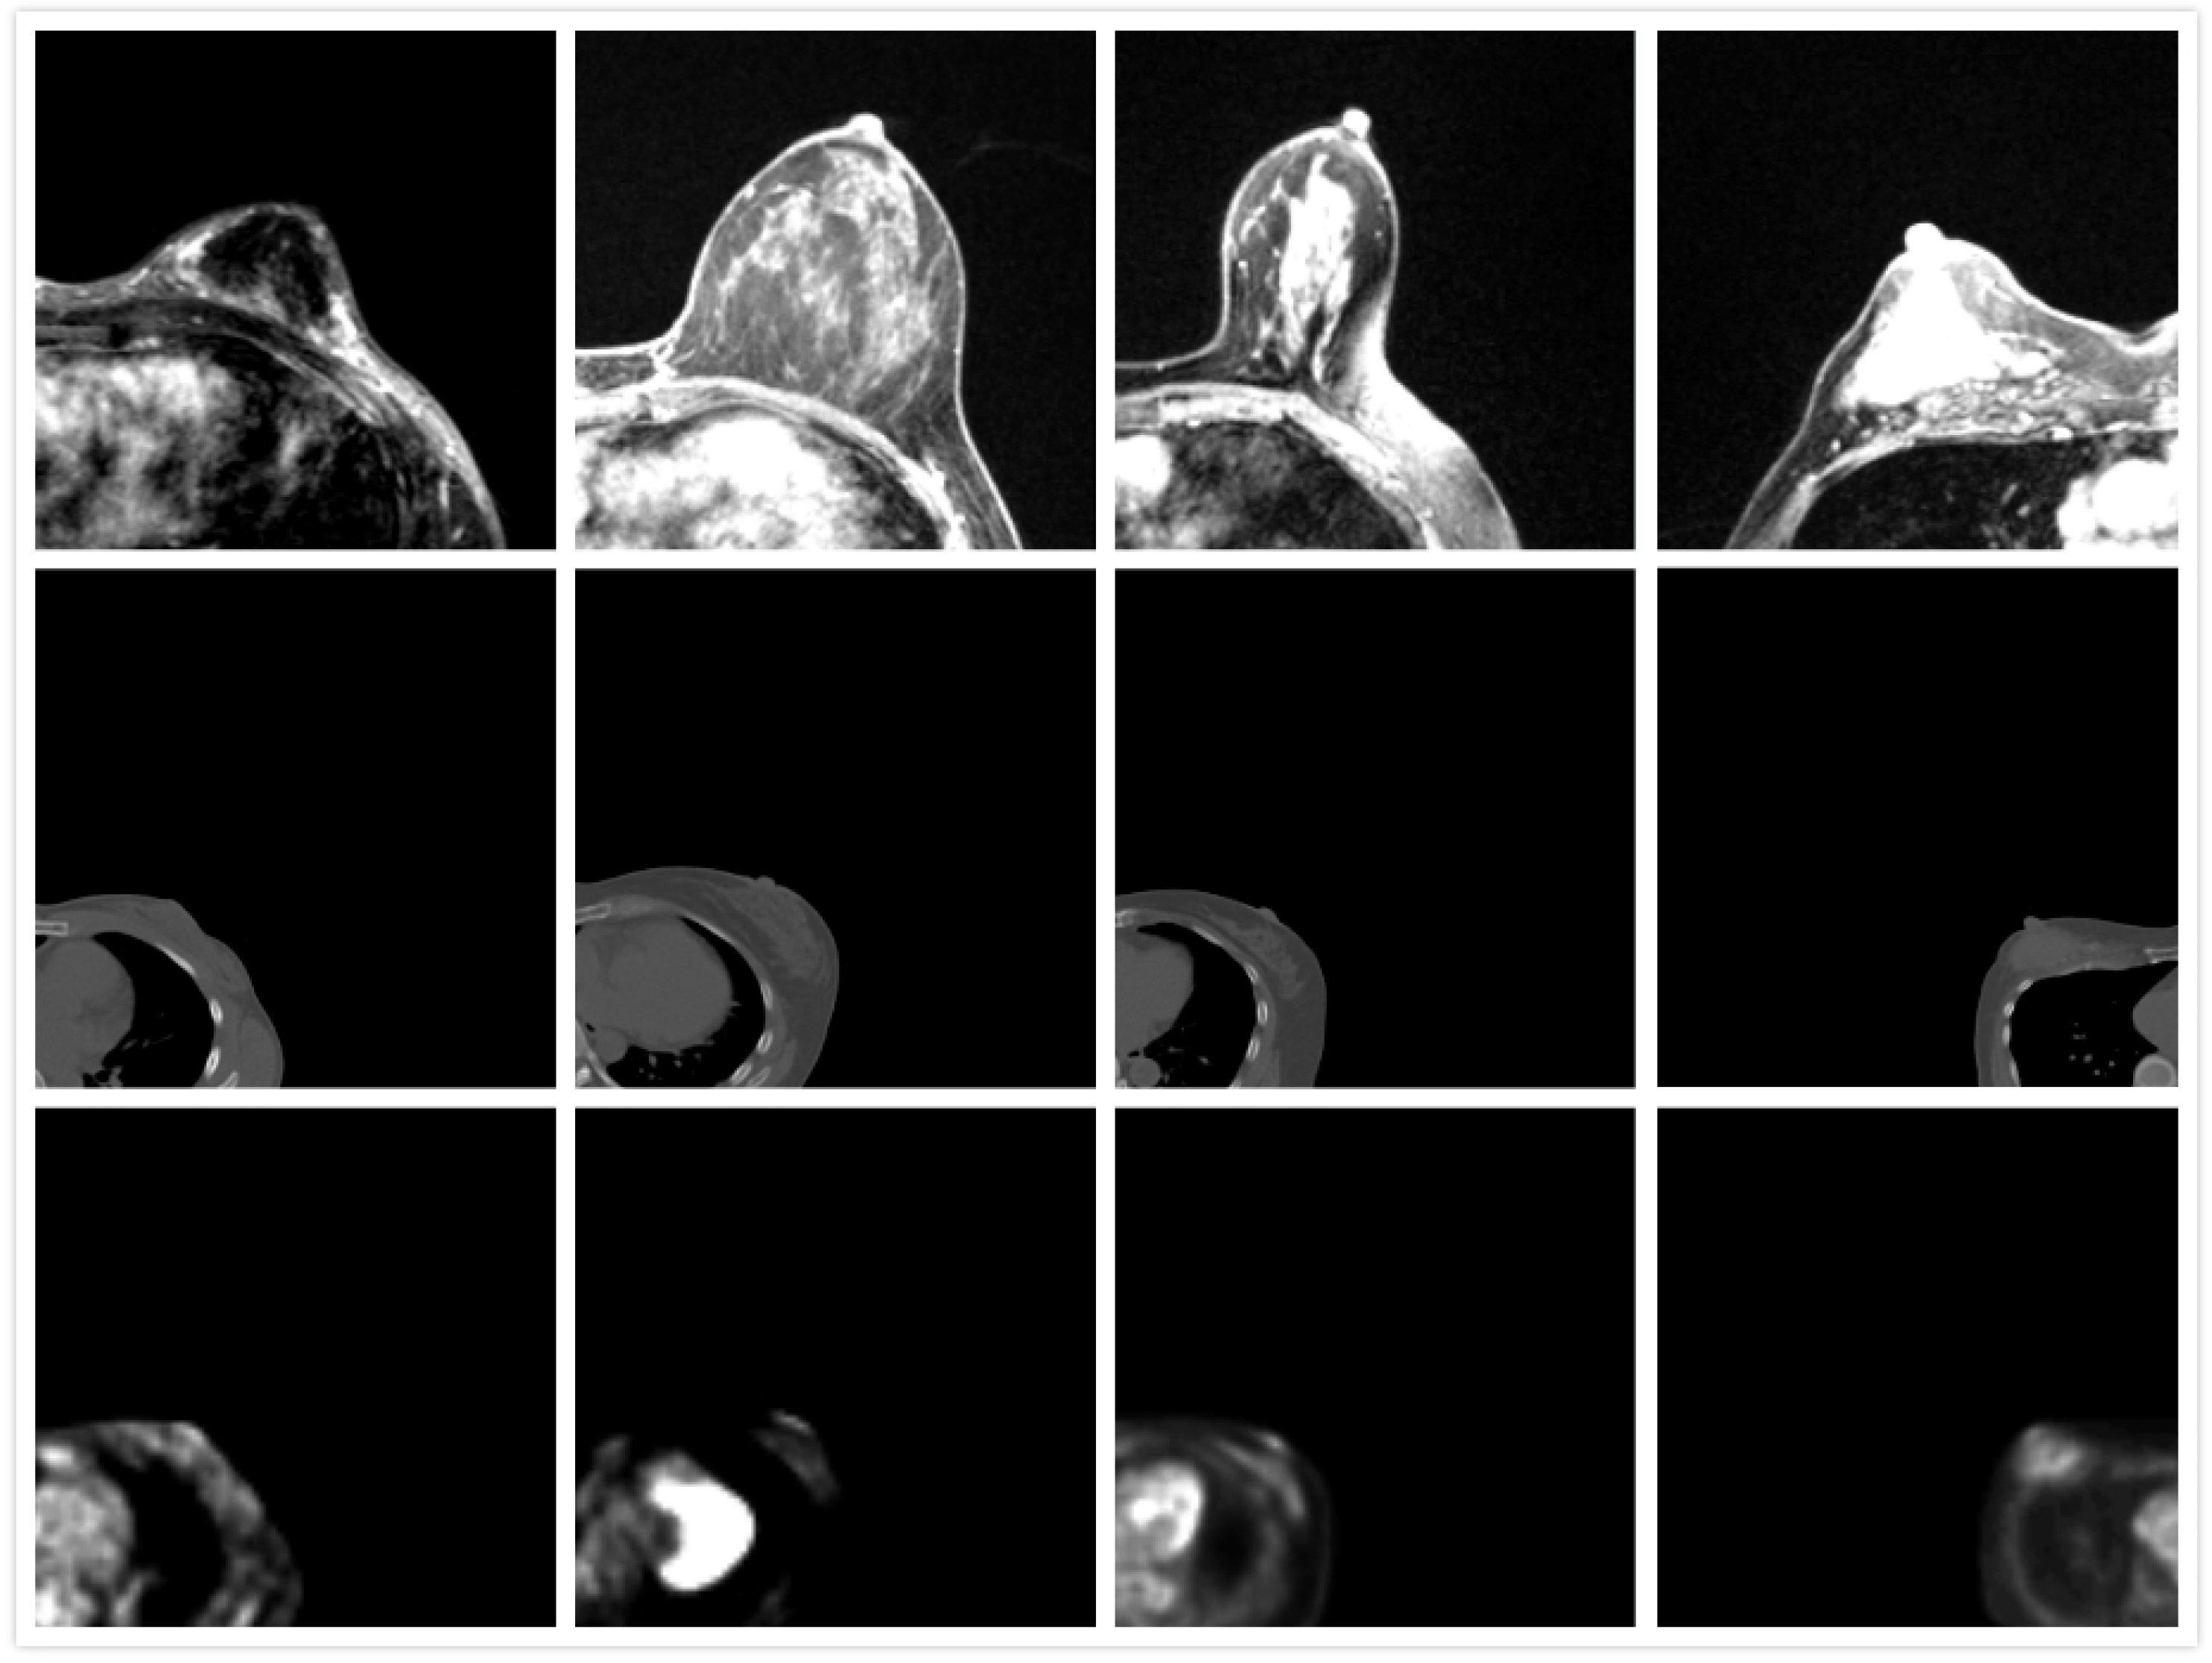

2.2. Modeling

2.2.1. Preprocessing

2.2.2. Patient-Specific Biomechanical Model

2.3. Optimization and Registration